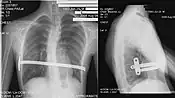

Técnica de Nuss

A técnica de Nuss é assim chamada pois foi desenvolvida pelo Dr. Donald Nuss, nos Estados Unidos. Trata-se de uma técnica minimamente invasiva que envolve, basicamente, a colocação de uma barra na caixa torácica. A barra é girada, empurrando o esterno e corrigindo a deformidade. A permanência da barra no tórax varia de acordo com o caso, sendo o mínimo de um ano, geralmente chegando a três anos.

Essa técnica cirúrgica é mais recomendade para ser realizada em pessoas que apresentem um pectus em "funil" (quando apresenta grande afundamento em um único ponto do tórax). De preferência a pessoa deveria ter menos do que 16 anos de idade, pois nessa idade o tórax é mais maleável. Também tem sido utilizada em outros tipos de pectus podendo obter bons resultados.

Essa técnica tem sido erradamente chamada de minimamente invasiva, mas na realidade trata-se de uma técnica de colocação de uma barra cirúrgica dentro da cavidade torácica e que tem a função de empurrar os ossos do tórax para fora.

A cirurgia é realizada no centro cirúrgico, sob anestesia geral e quando bem indicada e bem executada dá bons resultados estéticos.